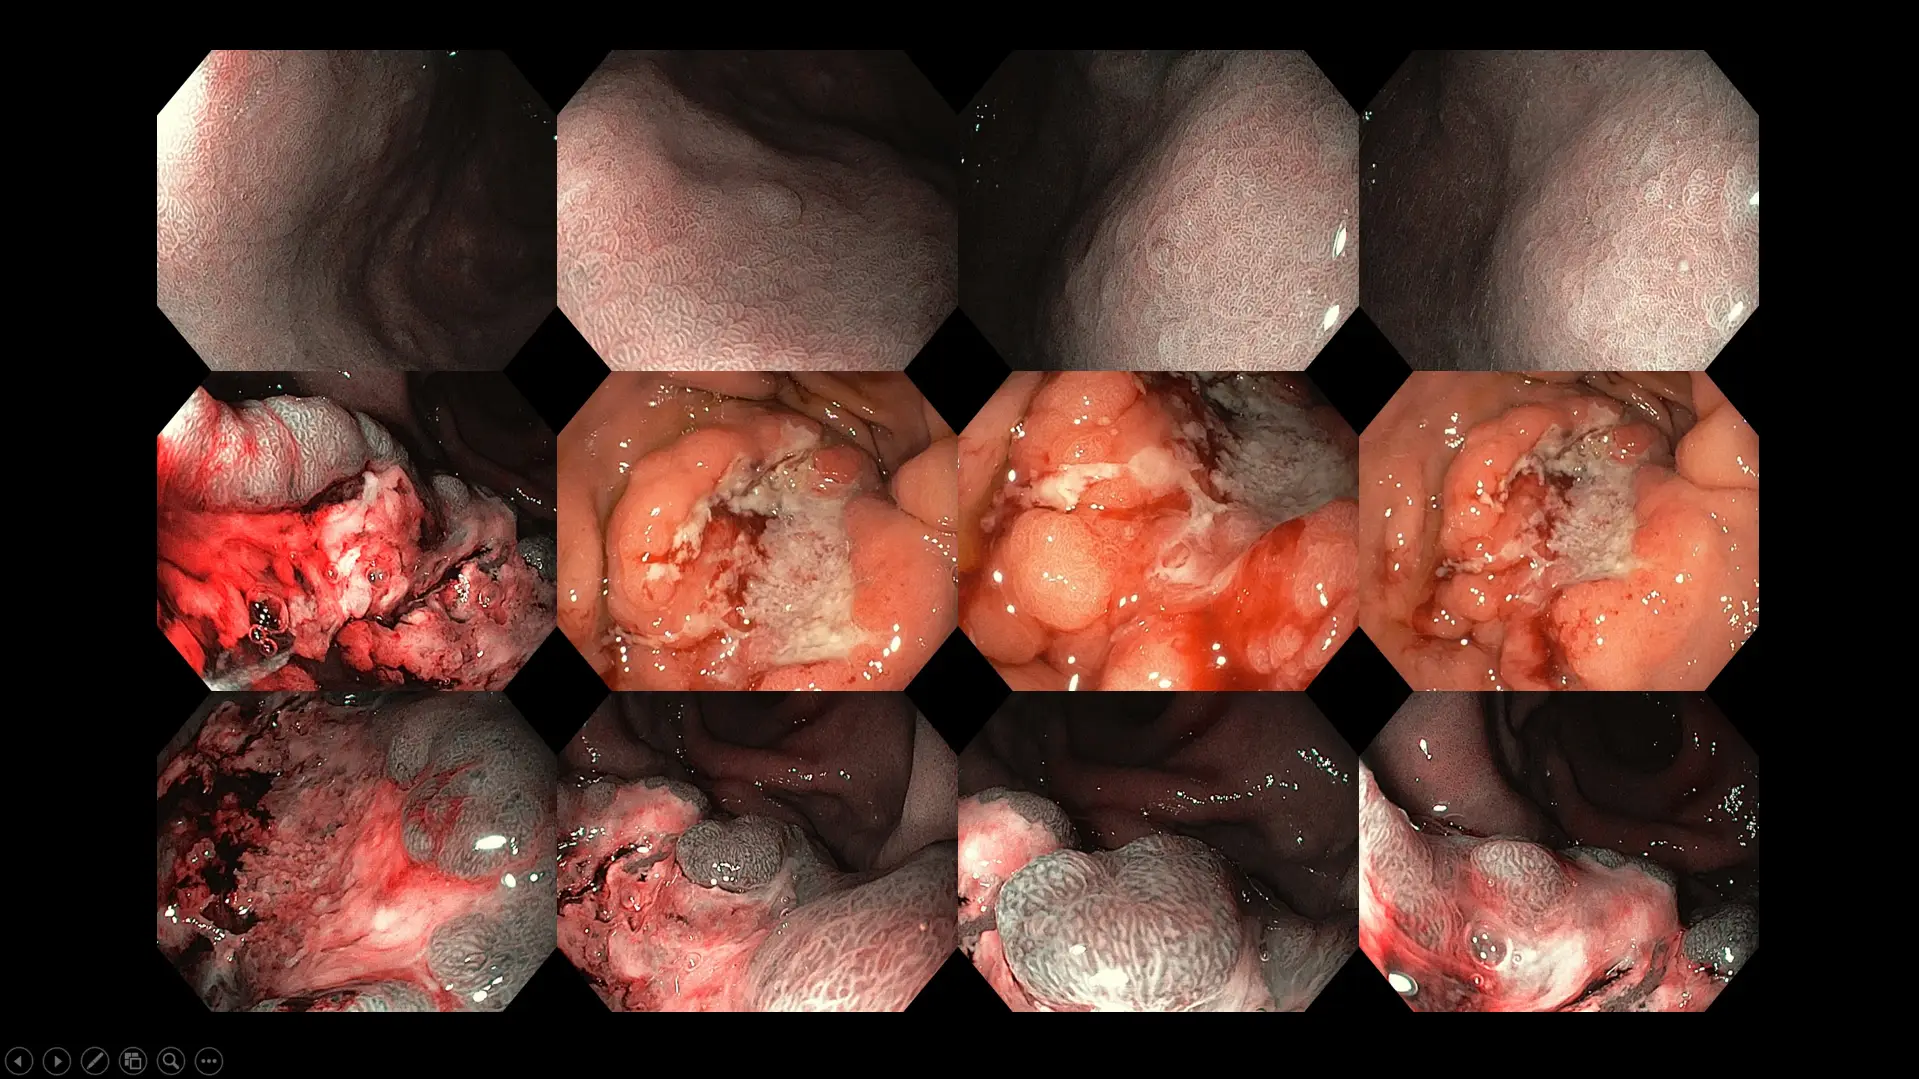

Figure 7: Case of advanced stomach cancer with Helicobacter pylori infection as background – the patient presented with bloatedness, abdominal discomfort, early satiety, loss of appetite, and weight loss over three months before seeking treatment.

Figure 8: Case of a large duodenal (first part of the small bowel) tumor in a patient with long-standing abdominal fullness, bloating, and mild crampy discomfort. Although surgical removal was offered due to the size of the polyp, our patient chose a conservative watch-and-wait approach because of her advanced age and multiple medical conditions.

Figure 9: Case of an advanced left-sided colon cancer in a patient who experienced new-onset constipation and bloatedness for six months before consulting a doctor.